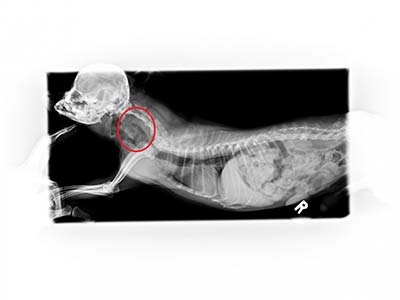

X光可以看到胃中有一根針

仰照也可以看到針的位置

內視鏡可以看到針卡在胃部